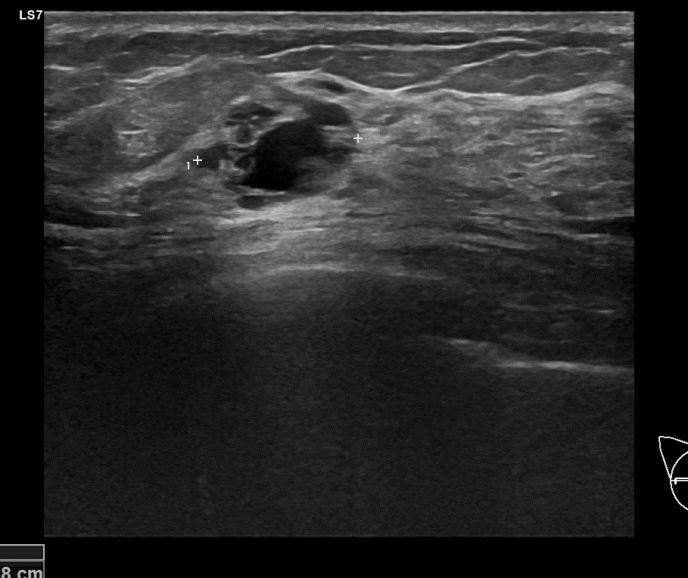

상기환자 외부검사상 이상소견으로 내원하신 50대 후반 여성분으로 우측 조직검사 시행해 침윤성 유방암으로 진단되었습니다